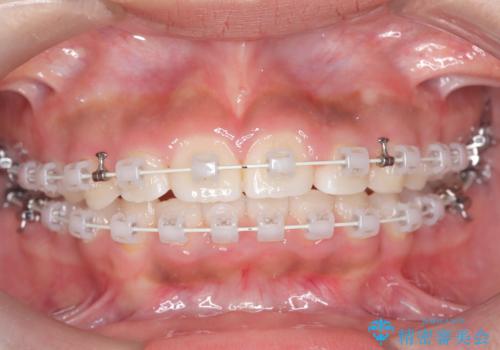

- 患者様は前歯の突出を主訴に来院されました。診査の結果、上顎の前歯が前方に傾斜しており、口元がやや突出して見える状態でした。一般的にこのようなケースでは抜歯矯正が選択肢となりますが、**患者様が抜歯を希望されなかったため、非抜歯での遠心移動(奥へ動かす治療)を計画しました。そのため、リンガルアーチ(歯の裏側に装着する装置)とTAD(歯科矯正用アンカースクリュー)**を併用し、上顎の歯を後方へ移動させながら噛み合わせを整える方法を選択しました。

まず、上顎にリンガルアーチを装着し、歯列の幅を適正に維持しながら遠心移動をサポート。さらに、**TAD(矯正用アンカースクリュー)**を利用することで、奥歯を固定源とせずに前歯だけを後方へ移動させることが可能になりました。これにより、抜歯をせずに前歯の突出を抑え、バランスの取れた口元へと改善。治療後、患者様からは「抜歯せずに理想の仕上がりになり、大満足」とのお声をいただきました。